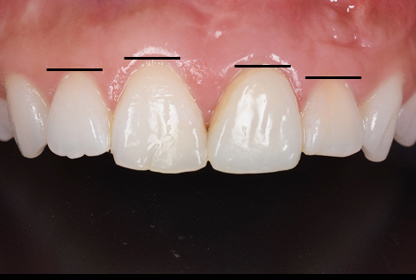

途中経過

歯の長さは、人それぞれになります。また、歯ぐきの位置も人それぞれになります。

患者さんによっては、歯ぐきの位置を揃えたいとおっしゃる方もいらしゃいます。そして、プラスαで歯をキレイに左右対称で仕上げたいとの希望でした。歯ぐきの高さを揃えるのは、解剖学的な幅を考えて歯肉の内側にある骨を削ることにより左右の歯ぐきの高さをある程度コントロールすることができます。

歯肉の手術をしてから、仮歯をセットして3ヶ月くらい状態を確認して最終的な型採り、試適、完成という流れとなります。多くの患者さんは、歯ぐきを手術するとなると一歩後ずさりをされますが、実際は、そこまで大きな手術ではなく1時間もかからずに終わるので、積極的になられても良いかもしれません。